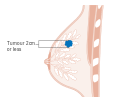

- Stage. Breast cancer staging using the TNM system is based on the size of the tumor (T), whether or not the tumor has spread to the lymph nodes (N) in the armpits, and whether the tumor has metastasized (M) (i.e. spread to a more distant part of the body). Larger size, nodal spread, and metastasis have a larger stage number and a worse prognosis.

The main stages are:- Stage 0 is a pre-cancerous or marker condition, either ductal carcinoma in situ (DCIS) or lobular carcinoma in situ (LCIS).

- Stages 1–3 are within the breast or regional lymph nodes.

- Stage 4 is 'metastatic' cancer that has a less favorable prognosis since it has spread beyond the breast and regional lymph nodes.

Stage T1 breast cancer

-